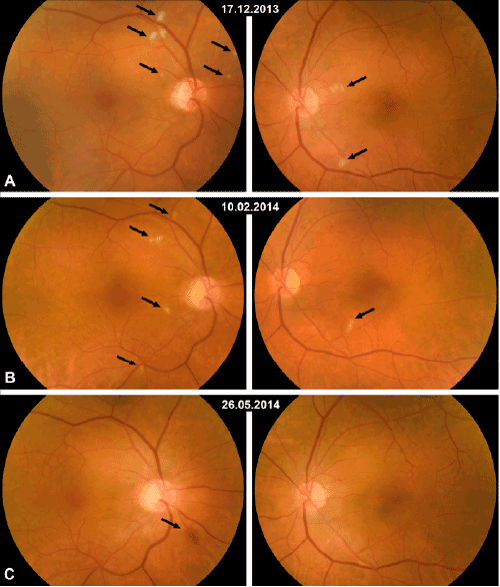

Figure 1: Examination revealed multiple asymptomatic Cotton-wool spots at the posterior pole of both eyes, which topography changed.